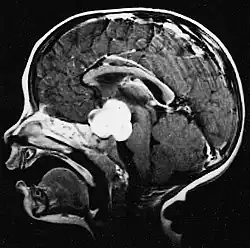

Usually – depending on the interview of the patient and after a clinical exam which includes a neurological exam and an ophthalmological exam – a CT scan and/or an MRI scan will be performed to confirm the presence of a tumor. They are usually easily distinguishable from normal brain structures using these imaging techniques. A special dye may be injected into a vein before these scans to provide contrast and make tumors easier to identify. Pilocytic astrocytomas are typically clearly visible on such scans, but it is often difficult to say based on imaging alone what type of tumor is present.